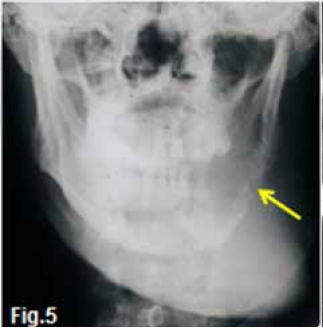

INTERPRETATION